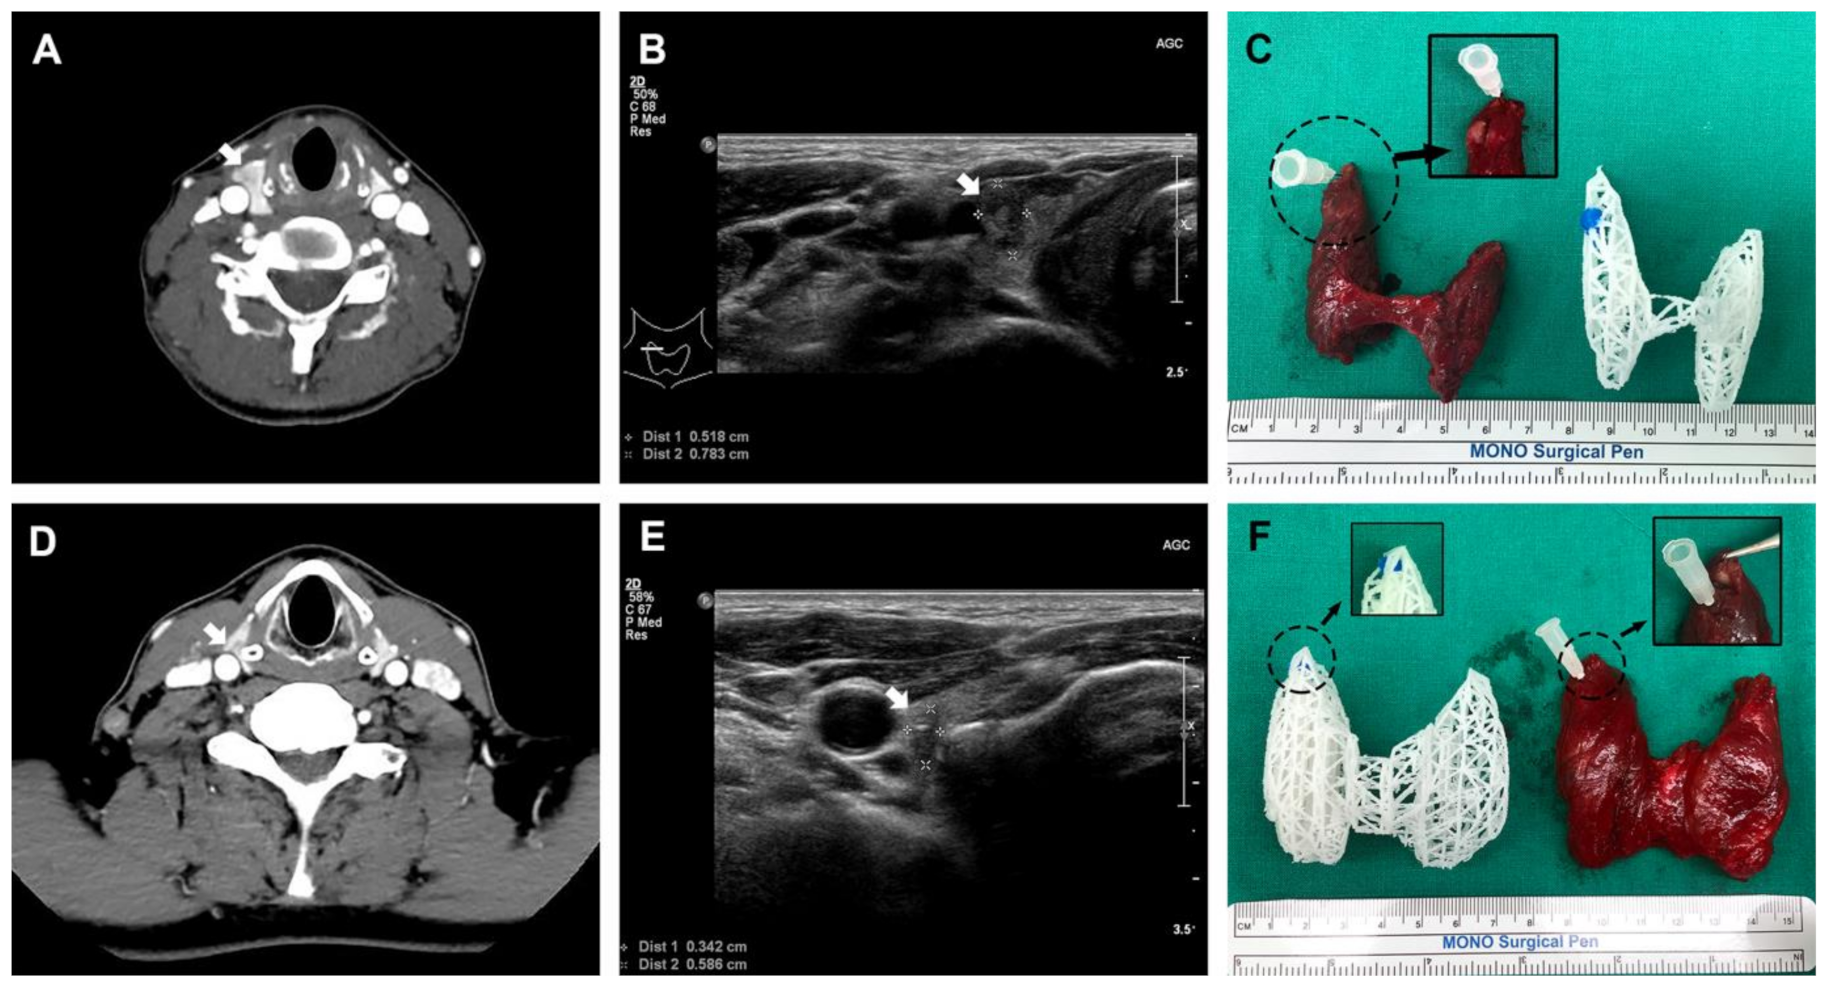

- Seok, J.; Yoon, S.; Ryu, C.H.; Ryu, J.; Kim, S.-K.; Jung, Y.-S. Mesh-type three-dimensional (3D) printing of human organs and tumors: Fast, cost-effective, and personalized anatomic modeling of patient-oriented visual aids. Appl. Sci. 2021, 11, 1047. [Google Scholar] [CrossRef]